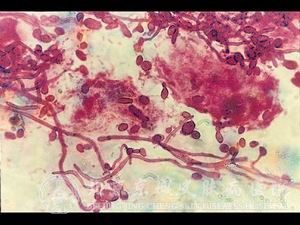

念珠菌病是什么?念珠菌病严重困扰着我们身边的很多人,很多患者关心这个念珠菌病是什么的问题,但目前有很多患者对念珠菌病是什么了解不足,错过了较佳念珠菌病治疗时机,从而导致念珠菌病病情发展严重,增加了念珠菌病患者的痛苦,同时也增加了念珠菌病的治疗难度。知道念珠菌病是什么,就可以及早的采取措施,预防念珠菌病的发生。

北京京城皮肤医院指出,念珠菌病在临床上可以分为念珠菌性外阴阴道炎和念珠菌性龟头包皮炎。常常会伴随尿频、尿急、尿痛。皮肤出现脓疱、结节、溃疡、瘙痒、囊肿等损害。